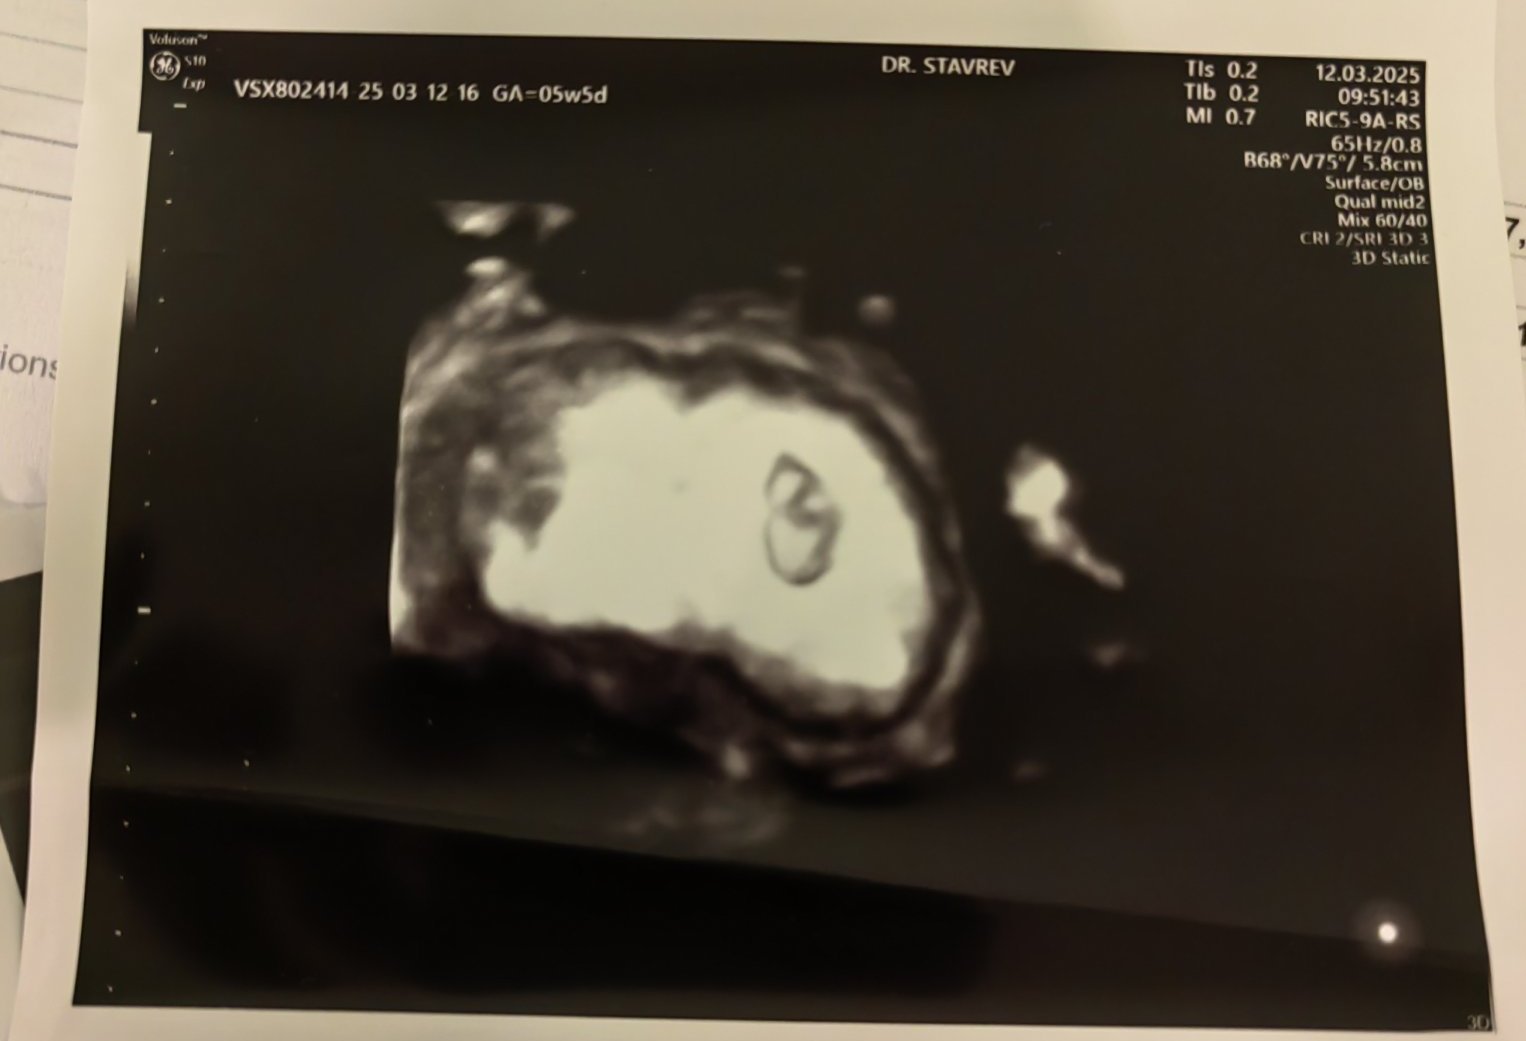

Кога обикновено може да се види ембрионът на ултразвукова снимка?